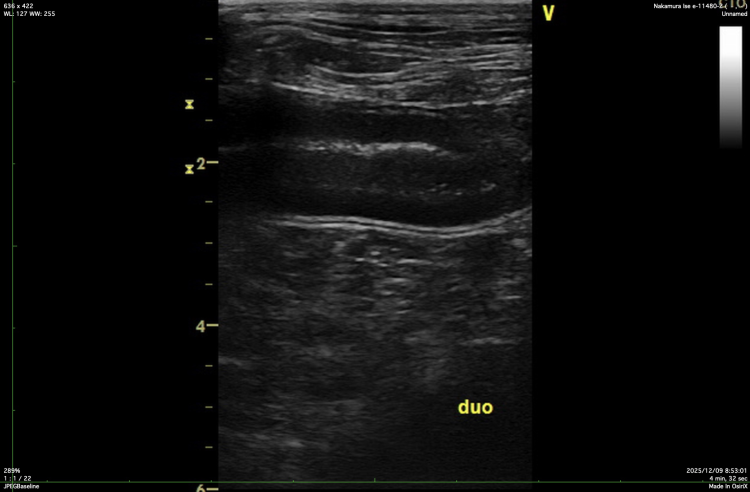

超音波(エコー)検査では、十二指腸の拡張を確認しました。

十二指腸のエコー画像